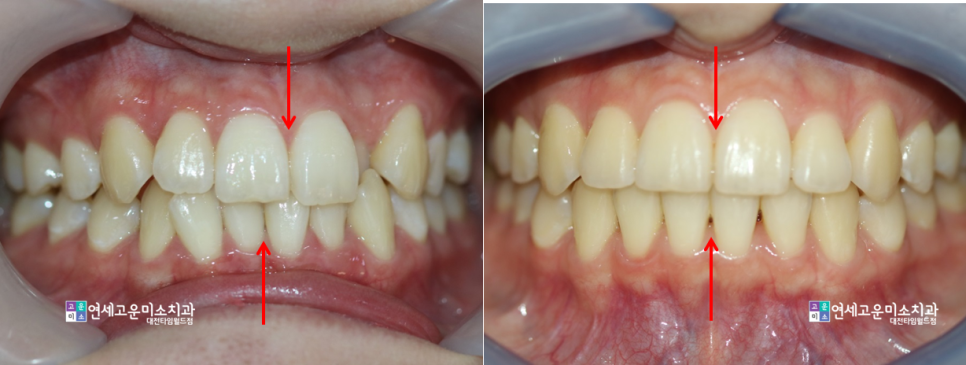

<앞니가 불규칙해요>

앞니가 불규칙한 상태로써,

상악 좌측과 하악 오른쪽의

치아들이 불규칙한 정도가

심한 편임을 알 수 있습니다.

덧니가 심한 쪽은 그쪽으로

공간 소실이 많이 일어난 것입니다.

그래서 윗니는 오른쪽으로

아랫니는 왼쪽으로 치우쳐졌고,

중심선이 어긋나게 되었습니다.

(빨간색으로 표시한 부분)